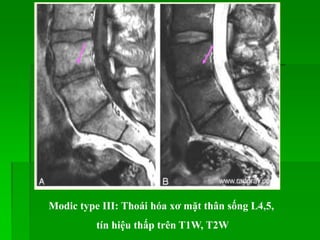

Các dấu hiệu thoái hóa cột sống:

 Đốt sống: thân sống giảm bề

cao,có gai xương, mặt thân sống

kém đều; mấu khớp thoái hóa (gai

xương, phì đại), bất thường tín

hiệu thân sống (Modic I,II,III).

 Đĩa đệm: giảm bề cao, mất nước

(tín hiệu thấp trên T2W), khí trong

đĩa đệm, rách bao xơ, lồi hay thoát

vị đĩa đệm.

Modic type I: thoái hóa viêm mặt thân sống L4,5, tín

hiệu thấp trên T1W, cao trên T2W, bắt Gd sau tiêm

Modic type II: Thoái hóa mỡ mặt thân sống L4,5, tín

hiệu cao trên T1W, T2W, tín hiệu thấp trên TIRM

T1W

T2W

TIRM

Modic type III: Thoái hóa xơ mặt thân sống L4,5,

tín hiệu thấp trên T1W, T2W